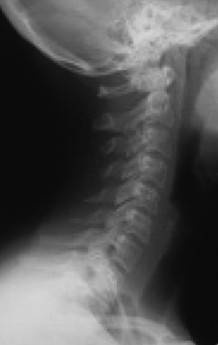

Причем, опять же, рост этого горбика она объясняет исключительно «солями» – остеохондрозом – и не связывает с изменившейся статикой своего позвоночника. В норме позвоночник, как известно, не должен быть прямым, как палка, а иметь физиологические изгибы. В частности, шейный отдел, состоящий из 7 позвонков, в норме должен быть чуть прогнутым внутрь (рис. 13).

Иллюстрация к книге — Биогимнастика для лица: система фейсмионика [i_018.jpg]

Рис. 13а. Спрямление шейного отдела